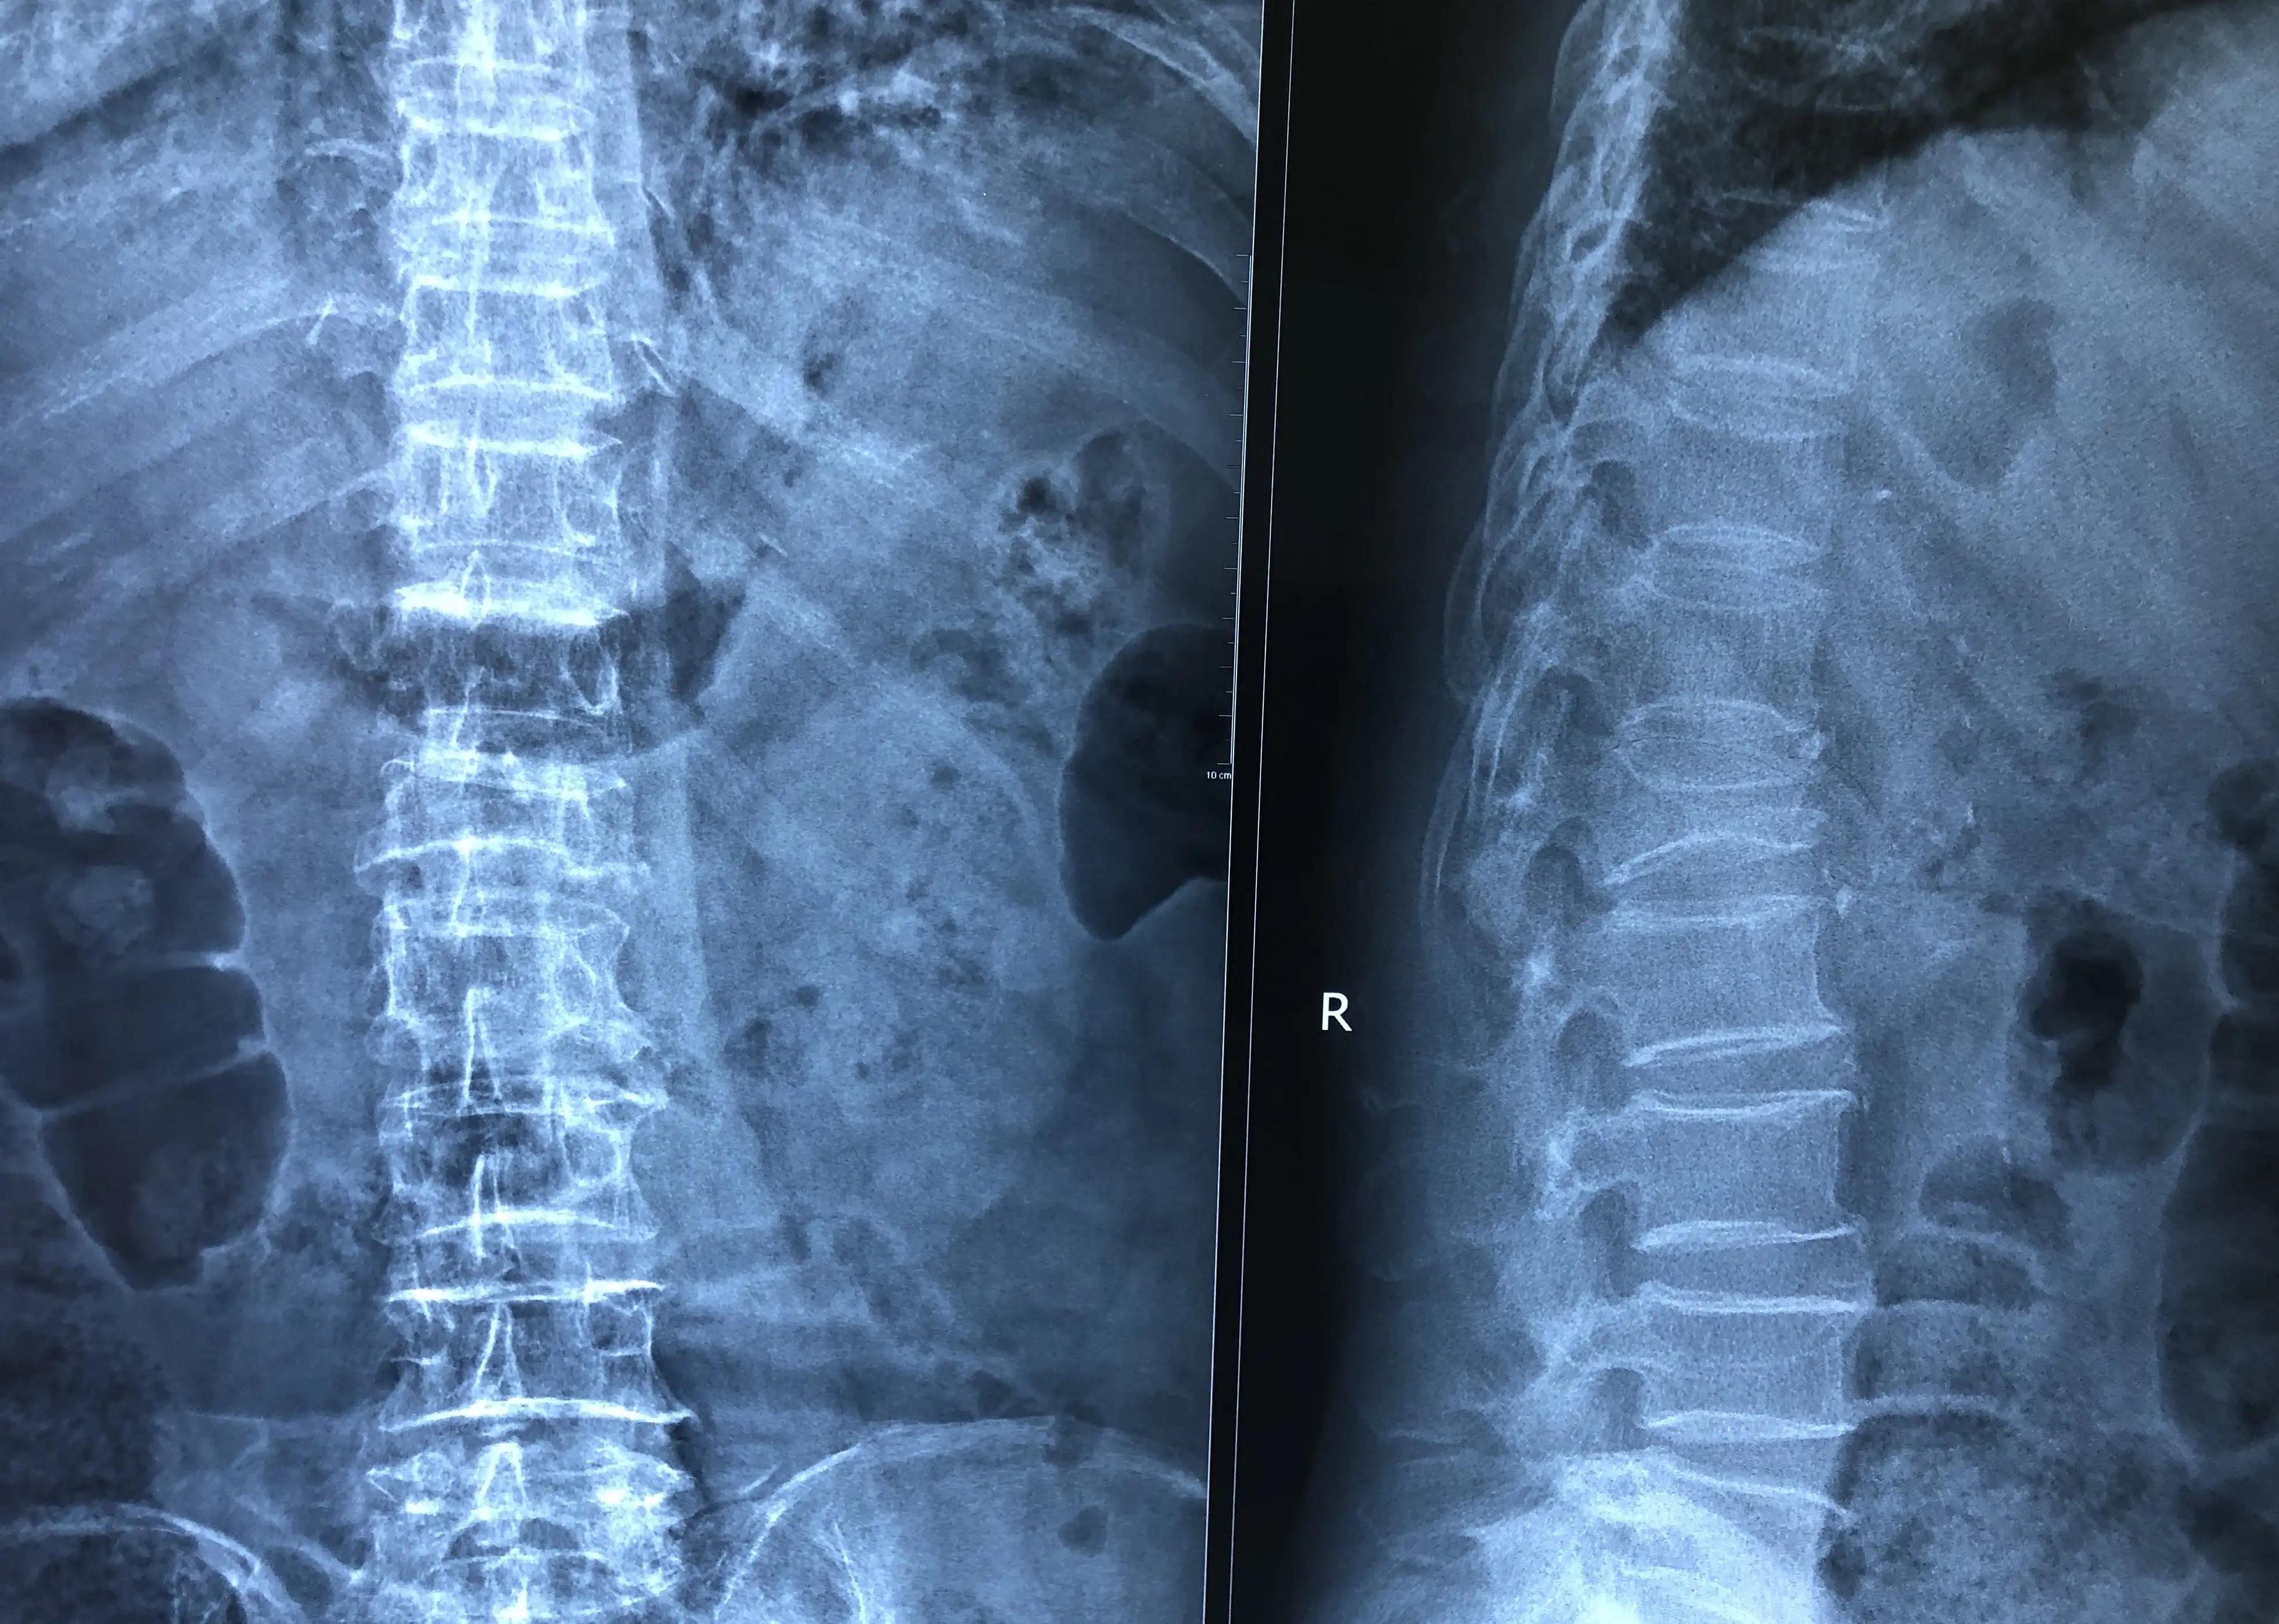

(2)X线检查 骨质疏松的X线表现主要是骨密度降低,表现为非承重区骨小梁稀疏、数量减少;骨的透光度增加;骨皮质变薄,皮质内哈佛管扩大出现皮质内隧道征、骨折。脊椎骨密度估计:I度为纵向骨小梁明显;Ⅱ度为纵向骨小梁变稀疏、表面粗糙:Ⅲ度为纵向骨小梁不明显。I度为可疑,Ⅱ度和Ⅲ度为骨质疏松。